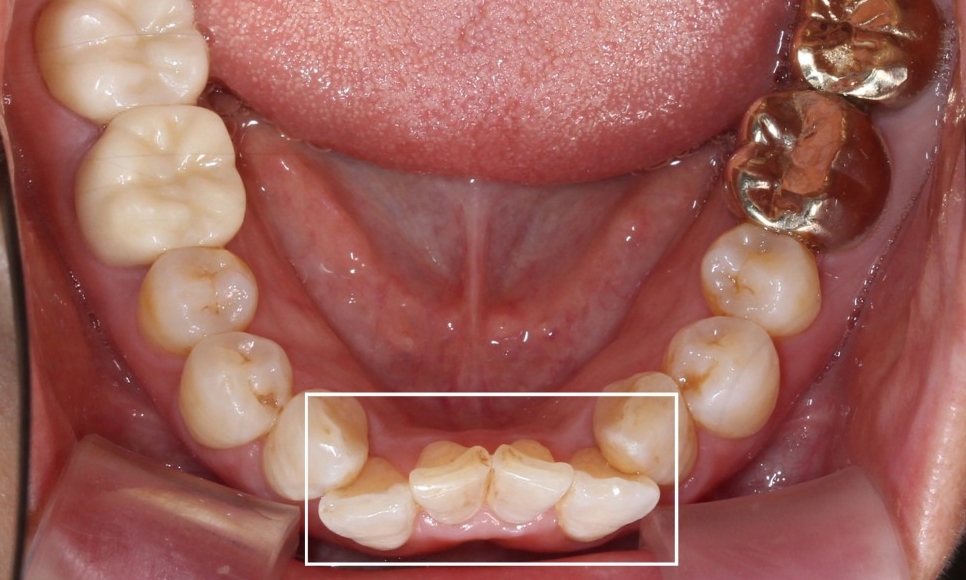

아랫니 부분교정 치료 후

2D치과 2D교정 전후사진

짜잔~!

아랫니 부분교정이 끝난 뒤의

치아 모습입니다.

약 9개월 정도 소요되었는데요^^

삐뚤거리던 아랫니가

정말 많이 정리된 모습이죠?

들쭉날쭉하던 아랫니의 전치부도

아랫니 2D교정으로

고르게 펼쳐진 모습입니다.

윗니에 가려져서

거의 보이지 않았던 아랫니도

2D부분교정을 통해

정상적인 교합상태로 바뀌었습니다.

과하게 물리는 모습이

많이 개선되었죠?